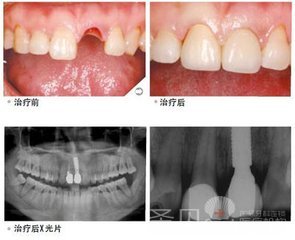

单颗种植牙多少钱?种植牙所具备的美观性以及具有的修复效果都是具有比较强大的优势,但对于很多修复患者而言,在采用比较好的修复方法时,其价格也是患者比较想了解的问题。下面我们就让为您详细介绍下。点击挂号为您节省宝贵时间

西安圣贝口腔医院介绍说:种植牙而言其价格的主要影响因素,与种植的技术、、同时还与自身的口腔环境与具体的情况等多方有很大的关系,一下就是关于单颗种植牙怎么收费的详细介绍: